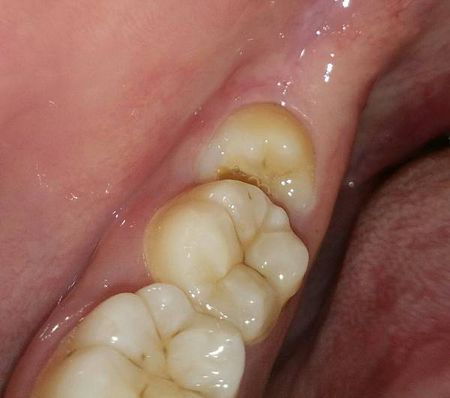

不需要拔的智齿图片

智齿图片

垂直阻生智齿